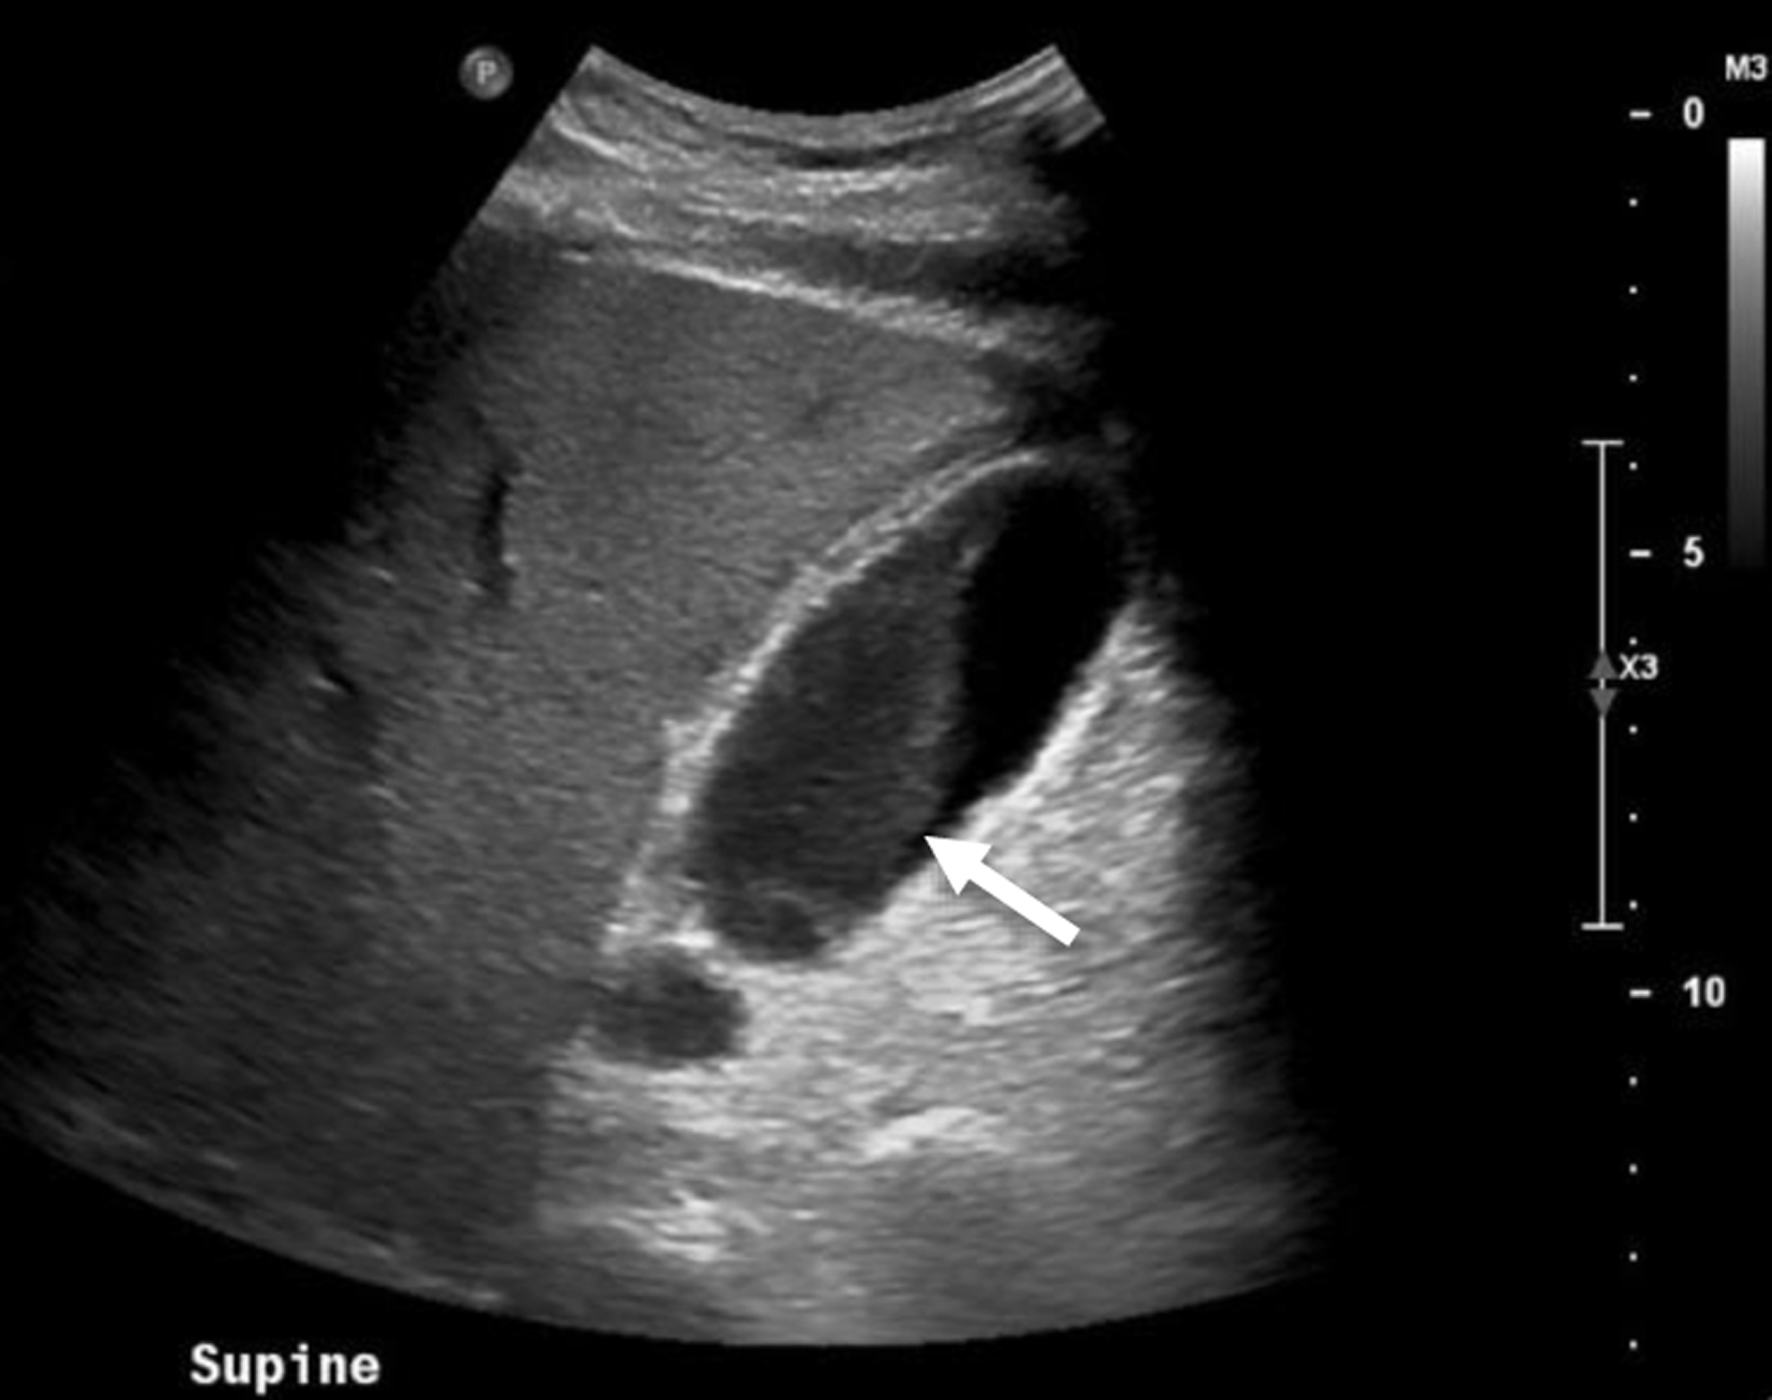

Gangrenous cholecystitis (GC) represents a severe complication of acute cholecystitis, characterized by full-thickness necrosis of the gallbladder wall. This condition arises from persistent cystic duct obstruction, causing local ischemia and inflammation. Its incidence ranges from 2% to 29.6% of acute cholecystitis cases and is associated with risk factors including male gender, age over 50, history of cardiovascular disease, diabetes mellitus (DM), and leukocytosis greater than 17,000 white blood cells/mL. GC carries significant morbidity and mortality, with increased operative complications compared to non-gangrenous acute cholecystitis. Early diagnosis and intervention are crucial to the prevention of disease progression and complications. Diagnosing GC preoperatively is challenging, particularly in diabetic patients who may lack typical symptoms such as right upper quadrant pain due to diabetic autonomic neuropathy. These patients often present with non-specific findings, increasing the difficulty of early diagnosis. This report presents a 56-year-old man with uncontrolled DM initially diagnosed with diabetic ketoacidosis (DKA), later found to have GC despite non-elevated liver function tests, absence of leukocytosis, and no reported history of postprandial or right upper quadrant pain. Despite imaging findings suggestive of acute cholecystitis, the absence of right upper quadrant pain and leukocytosis lowered clinical suspicion, leading to delayed diagnosis and intervention. Ultimately, intraoperative findings confirmed GC, and the patient underwent a successful laparoscopic cholecystectomy. This case highlights the complexities of diagnosing GC in diabetic patients and suggests that underlying microvascular disease and autonomic neuropathy contribute to atypical presentations. Clinicians should consider GC in diabetic patients with non-specific abdominal symptoms and maintain a low threshold for surgical intervention. Further studies are needed to elucidate the pathophysiology and clinical presentation of GC in diabetic patients and to optimize diagnostic and management strategies.